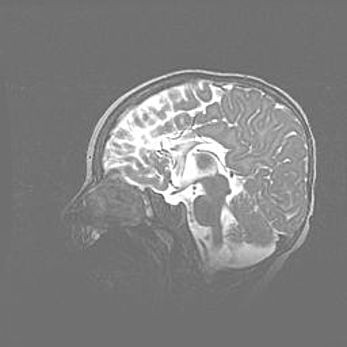

Неполная лизэнцефалия (пахигирия). Открытая гидроцефалия.

Возраст: 17 дней

Вес: 3110 г

Пол: мужской

Окружность головы: 33,5 см

Срок гестации: 35-36 недель

Лизэнцефалия—недоразвитие корковой пластинки и мозговых извилин в результате нарушения миграции нейронов коры. Поверхность мозговых полушарий гладкая. Микроскопически выявляется отсутствие нормальных слоев коры и скопление групп нейронов в подкорковом белом веществе.

Пахигирия—уменьшение числа вторичных извилин. В пораженном полушарии нервные клетки образуют толстый недифференцированный слой с неправильно расположенными нервными волокнами и группами гетеротопных клеток. Нервные клетки незрелые. Белое вещество истончено. При этом нередко аномально развит корково-спинномозговой путь.